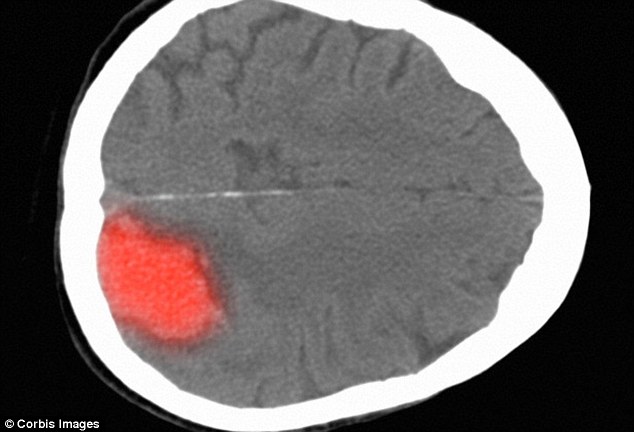

A CT scan of the brain after a stroke. Cooler temperatures may trigger strokes because exposure to the cold has various effects on the body. These range from increased blood pressure to thicker blood